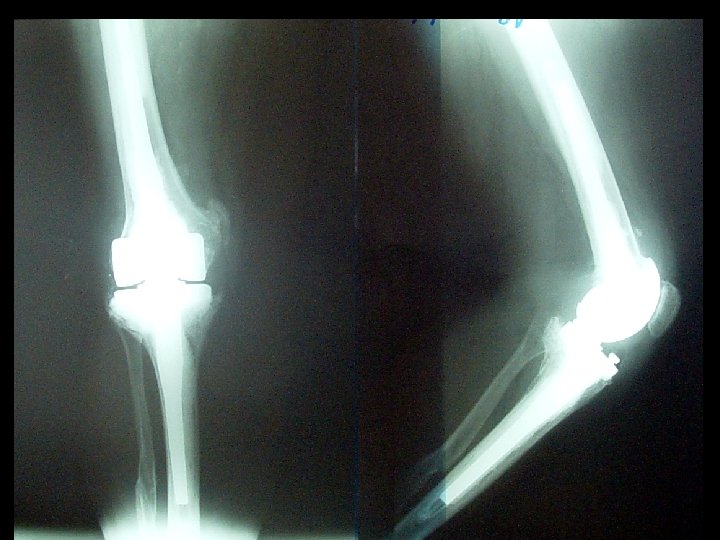

Our experience 527 total knee replacements with mobile bearing Period 1987 - 2005 48% left knee, 52% right knee 94 male, 433 female

Range of motion